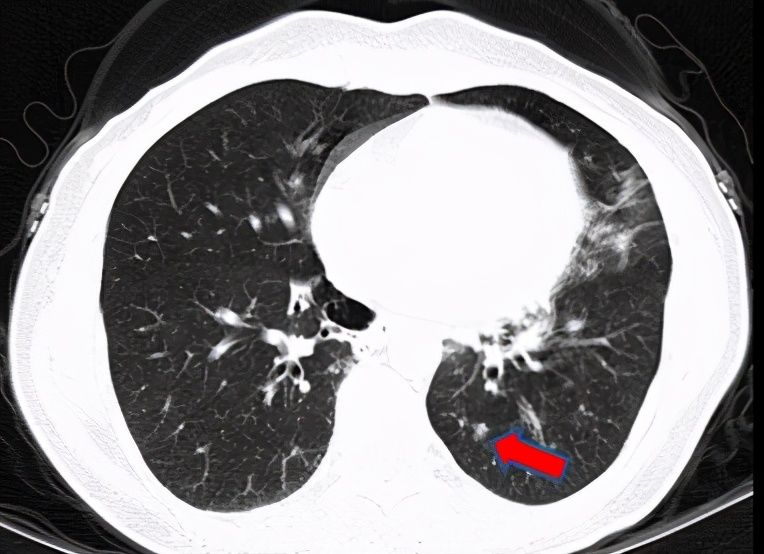

医生给陈小姐安排了抽血检查,发现她的炎症指标中度升高,再结合她的病程胸部CT表现,考虑慢性低毒力的病原体引起的肺部感染可能大。有了大致的方向,医生给陈小姐安排了支气管镜检查。取到的标本做了微生物检测,包括传统的培养检查和新兴的基因检测,检出了少见的“盖尔森基兴诺卡菌”,完美证实了医生的推测。经过一系列抗感染治疗,陈小姐随访胸部CT左下肺病灶逐步吸收。